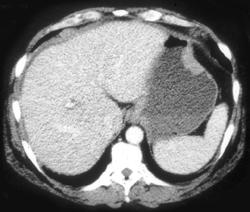

GIST Tumor